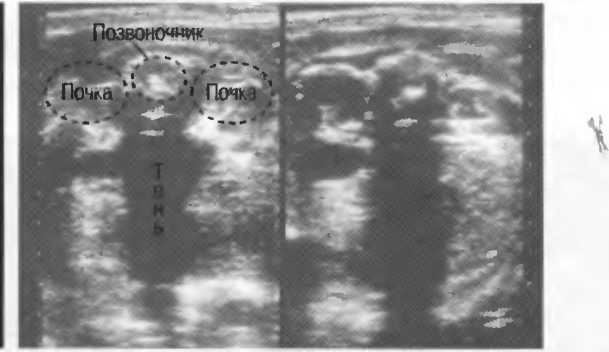

4. У здоровых обследуемых паренхима печени должна быть немного более эхогенна. чем кора рядом расположенной почки (рис. 26).

Рис.26. Продольный срез через печень и правую почку: нормальная паренхима печени более эхогенна, чем паренхима нормальной почки. Это еще один способ проверки качества изображения.